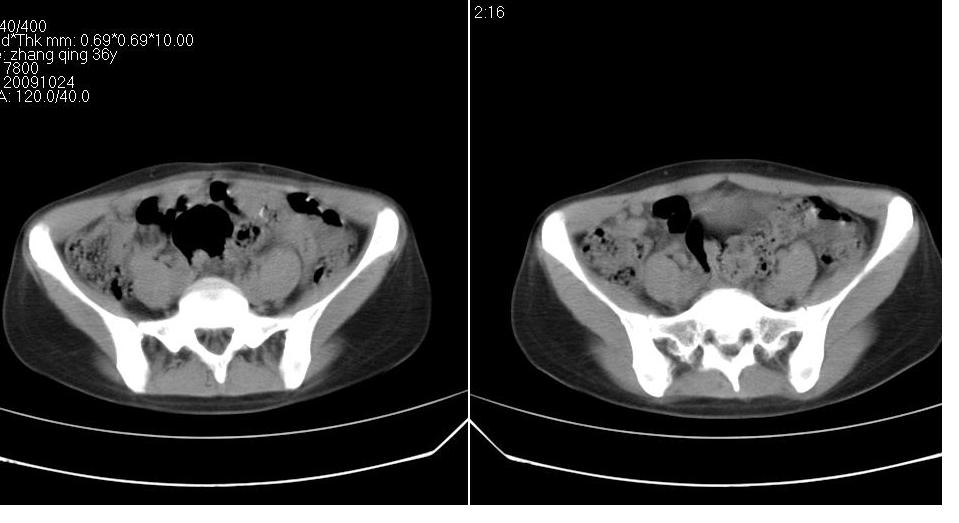

标题: CT22811:女 36岁,B超提示右侧附件囊性占位。 [打印本页]

标题: CT22811:女 36岁,B超提示右侧附件囊性占位。

右侧卵巢囊肿

右侧卵巢囊肿。

支持右侧附件良性囊性占位性改变。

手术结果证实为右侧输卵管囊肿。

输卵管囊肿罕见,从影像上无法同卵巢囊肿区分。

还是报右侧附件区良性囊性占位性改变       至于输尿管或卵巢囊肿不太好鉴别